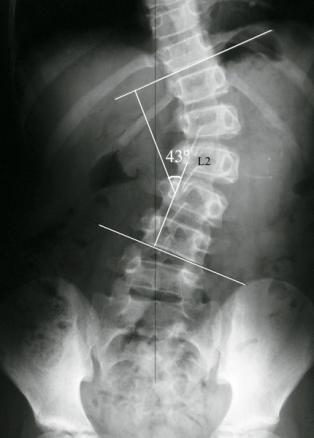

Mesure de l’angle de Cobb d'une socliose

La mesure de l’angle de Cobb permet de quantifier l’importance de la déformation frontale.